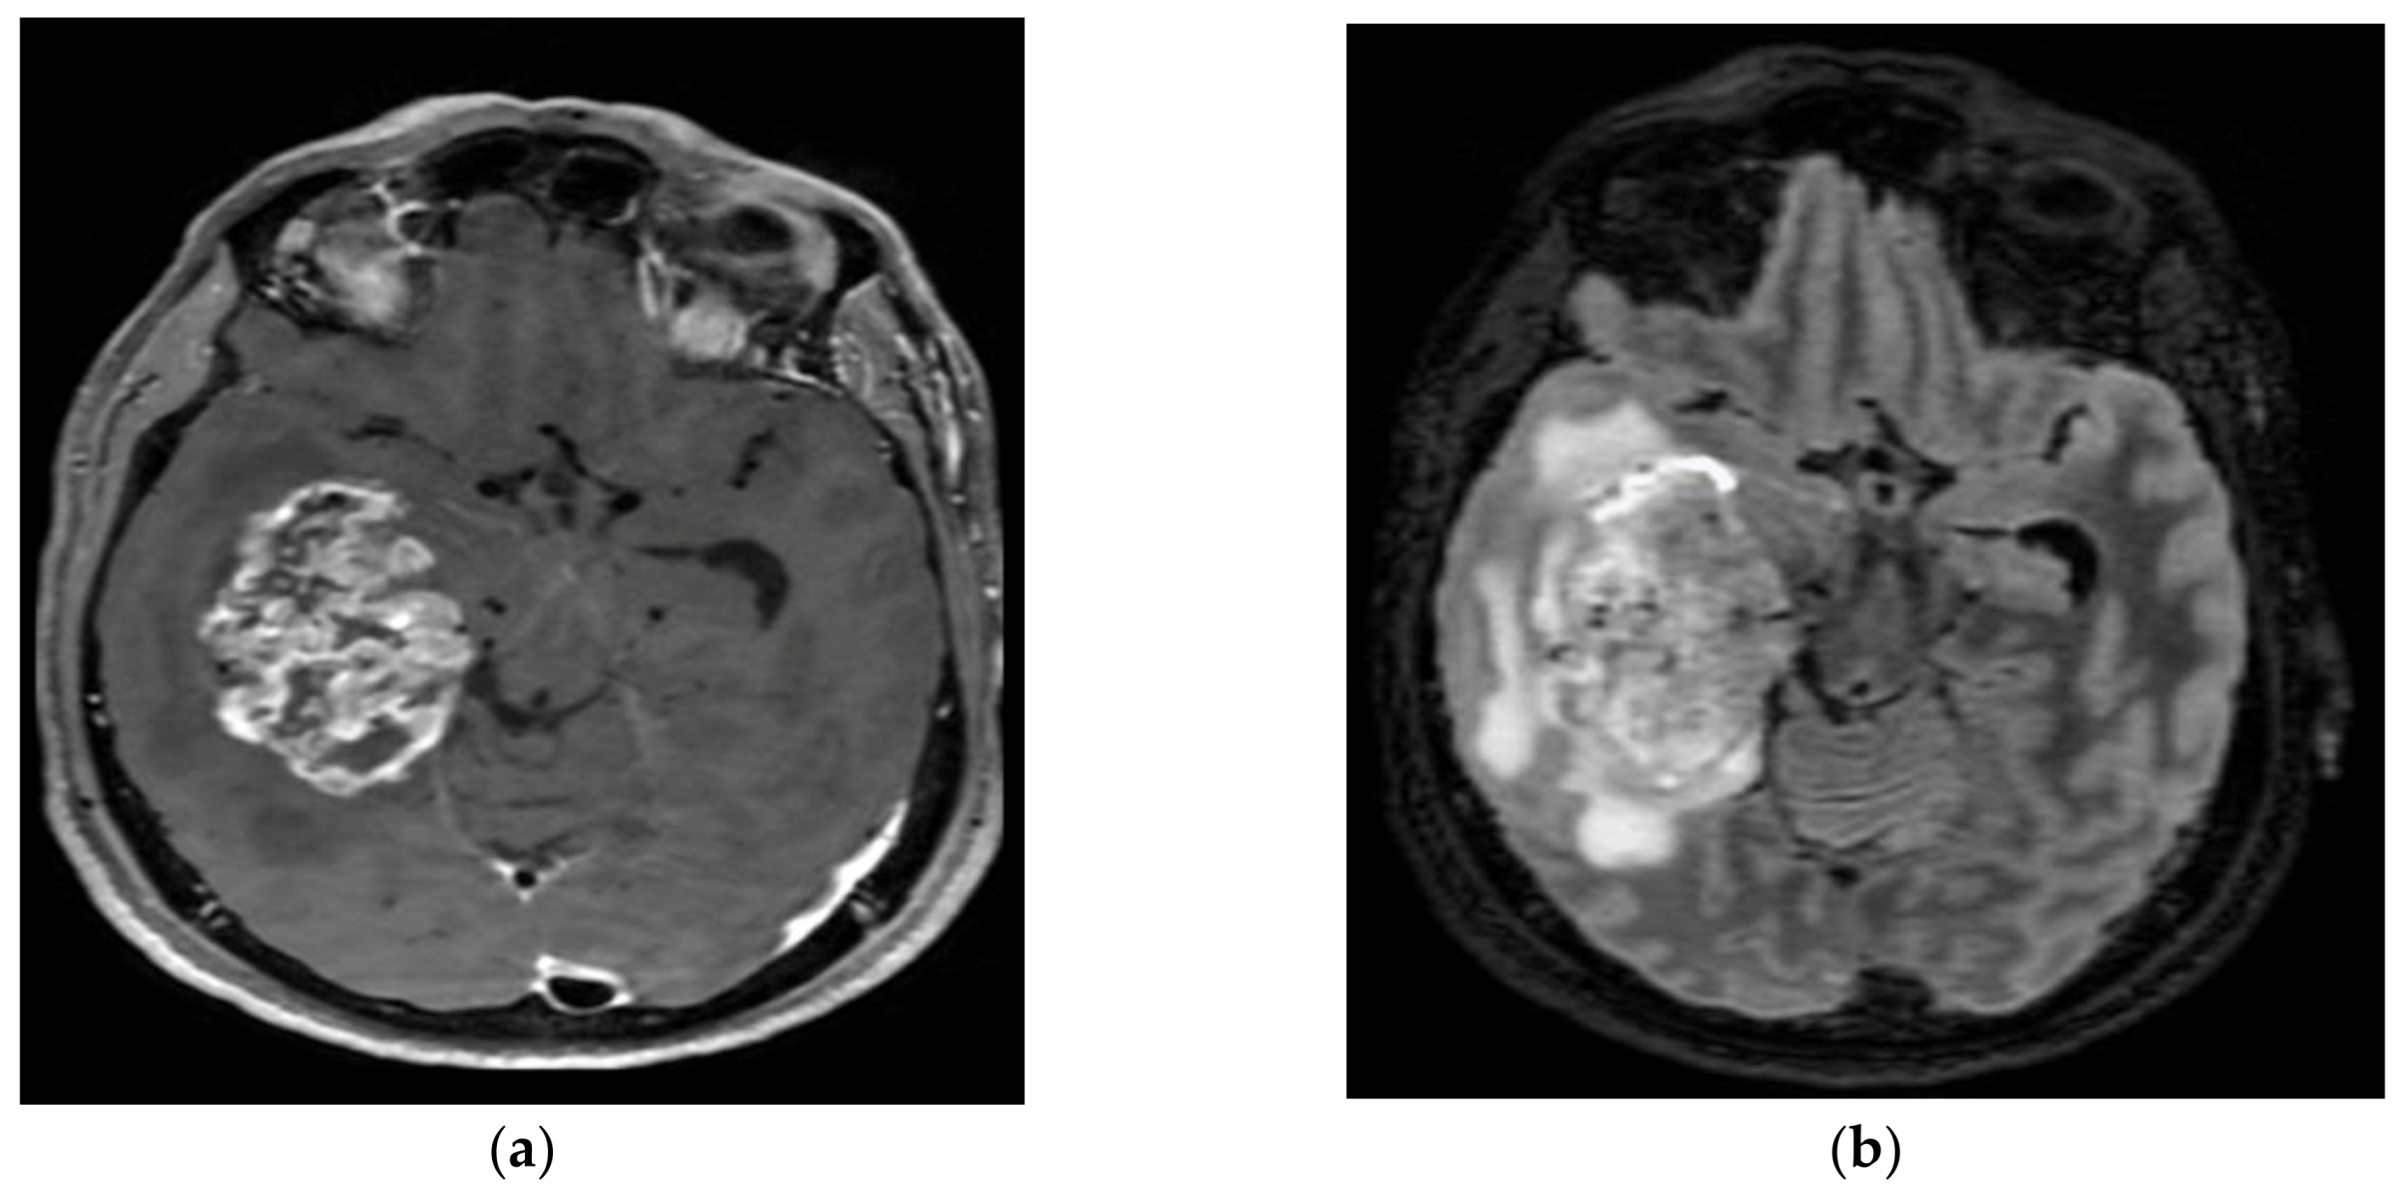

4.1. Pilocytic Astrocytomas